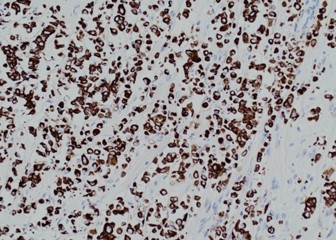

Pathology of the right hemicolectomy specimen was “involvement by metastatic carcinoma, immunoprofile compatible with breast primary”. The cytokeratin profile was CK7+, GATA3+ and MOC-31+, and negative for CK20 and CDX-2. There was very focal positivity for E-cadherin, while p120 catenin mostly showed cytoplasmic staining in the tumour cells. Microscopic examination suggested that the tumour invaded from mucosal side of the intestinal towards the serosa; the proximal and distal resection margins were clear. The morphology and immunoprofile point towards a metastatic carcinoma of breast.